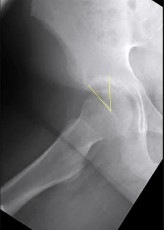

A 12-year-old male with a BMI > 95th percentile presents with hip pain and is diagnosed with a Slipped Capital Femoral Epiphysis (SCFE). Which of the following is the strongest indication for prophylactic in situ pinning of the asymptomatic contralateral hip?

Correct Answer: Underlying endocrinopathy, such as hypothyroidism

Explanation:

Prophylactic pinning of the contralateral hip in SCFE is controversial but is strongly indicated in patients with underlying endocrinopathies (e.g., hypothyroidism, growth hormone deficiency) or renal osteodystrophy. These conditions dramatically increase the risk of bilateral involvement. Other indications include inability to follow up, radiation therapy, and open triradiate cartilage (though age and triradiate status are debated, endocrinopathy is universally agreed upon).

A 13-year-old overweight male presents with an acute exacerbation of chronic right groin and knee pain. He walks with an externally rotated gait. Radiographs confirm a severe Slipped Capital Femoral Epiphysis (SCFE). Pathophysiologically, the slippage in SCFE occurs primarily through which specific histological zone of the proximal femoral physis?

Correct Answer: Zone of hypertrophy

Slipped Capital Femoral Epiphysis (SCFE) typically occurs due to mechanical shear forces across a weakened physis during the adolescent growth spurt. Histologically and biomechanically, the weakest layer of the growth plate is the zone of hypertrophy. The slippage classically occurs through this layer because the chondrocytes are enlarged, and the extracellular matrix is sparse compared to the reserve or proliferative zones, making it highly susceptible to shear stress.